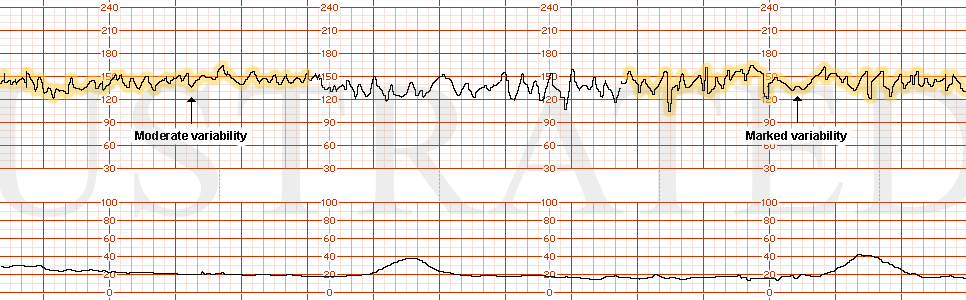

STRIP 76

1. Ctxs – 11 contractions each 50 sec 55 sec 50 sec, etc duration (3rd contraction from end too long)

Baseline -140bpm with mod variability -7-8 bpm

Decels - None

Accels – None until scalp stimulation to be written on strip done at 14 min into strip – 18 bpm x 20 sec

Ctxs2 – 10 contractions – each 60, 65, 60, 65 etc sec duration.

Baseline2 – 150 bpm with mod variability 7-8 bpm

Decels2 - Late Decel with Ctx 2, Ctx 8 (more gradual, less variable looking), each 15 bpm nadir

Variability2 – moderate at 7-8 bpm

Accels2 – none scalp stim not done.